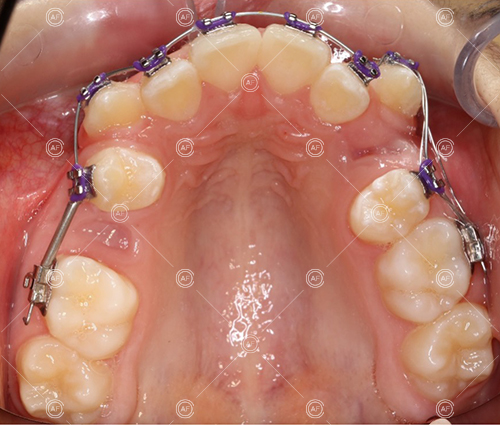

- Extraction of upper right 5, upper left 4, lower left 5, lower right 5

- Fixed appliances in the upper and lower arches

Treatment progressed by starting with thin, flexible nickel titanium archwires of a round diameter, transitioning to a rectangular nickel titanium archwire before eventually working up to a working archwire (1925 stainless steel).

Residual space from the extractions were closed using upper and lower nickel titanium closing coils. Class 2 elastics were used to facilitate space closure in order to gain class 1 buccal segments.